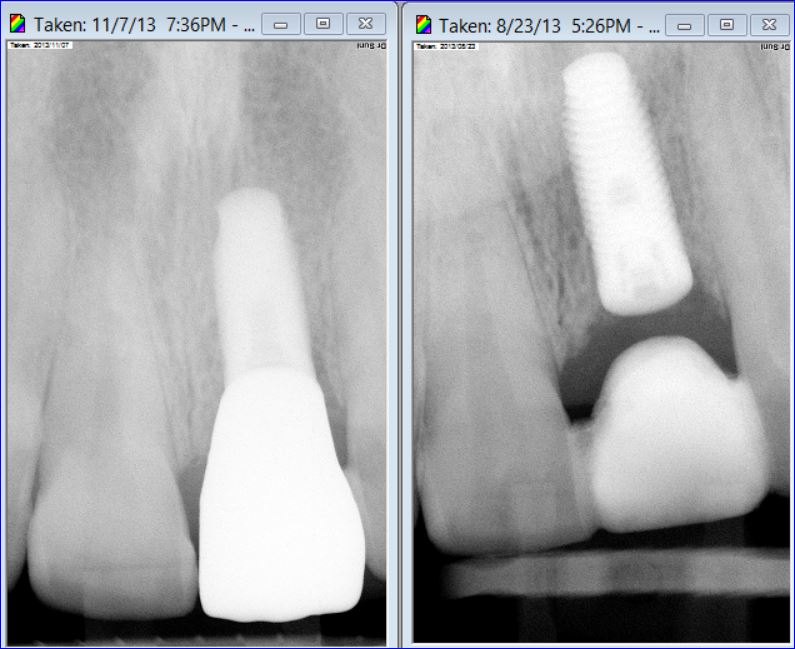

ANTERIOR IMPLANT

A graduate student came to our DENTOLOGY practice with a broken upper front tooth. Dr. Andrews recommended to replace it with a dental implant. Due to high smile line and anatomy of the area, this type of cases is considered to be one of the most challenging for a dentist to treat.

Without any incisions, Dr. Andrews removed the broken root and placed an implant along with a bone graft during the same surgery. Immediately, a temporary crown was attached to two other front upper teeth to form the ideal shape for the soft tissue profile. A few months later, 3D Intraoral scan was taken and Dr. Andrews used Virtual Prosthodontics (CAD) and Reverse Restorative Rehabilitation Protocol to design Full Contour Zirconia (FCZ) screw-retained Implant Crown.

Then the crown was milled (CAM) and sintered by a specialized Milling Center. Once it had been received, the FCZ restoration had been custom shaded and glazed at DENTOLOGY in-house lab. During the patient’s next and final visit, all-ceramic crown was delivered via screw-retained fashion to prevent any complications associated with cement retention under the gum margin (the most common reason for implant failures in intraorally cemented cases).